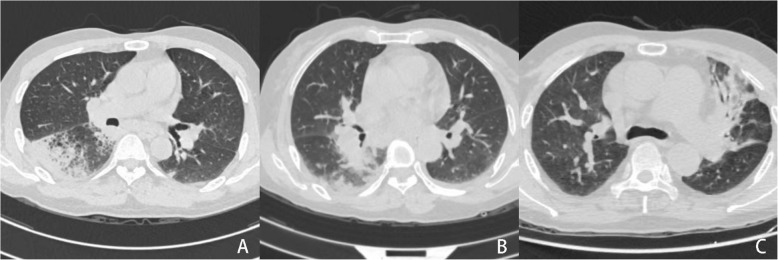

Background: Recently, increased reports reveal that anti-interferon-gamma (IFN-γ) autoantibodies (AIGAs) are strongly associated with several severe disseminated infections. However, reports on AIGAs with central nervous system (CNS) infections are rare. Here, we described three AIGAs-positive adults who had persistent or recurrent disseminated infections caused by Talaromyces marneffei (TM), nontuberculous mycobacteria (NTM), mycobacterium tuberculosis (TB), or other pathogens, accompanied with CNS infections. In addition, we conducted a thorough literature review of AIGAs-positive patients with CNS infections.

Case presentation: We report three HIV-negative cases of recurrent disseminated infections including CNS, and AIGAs were measured. All patients had no history of underlying diseases or immunosuppression and presented with fever, cough, and headache. They were negative for HIV antibodies but positive for AIGAs. The patients were diagnosed with CNS infections based on cerebrospinal fluid (CSF) examination and next-generation sequencing (NGS). All patients received anti-infective treatment according to different pathogens, and their condition remained stable without recurrence.